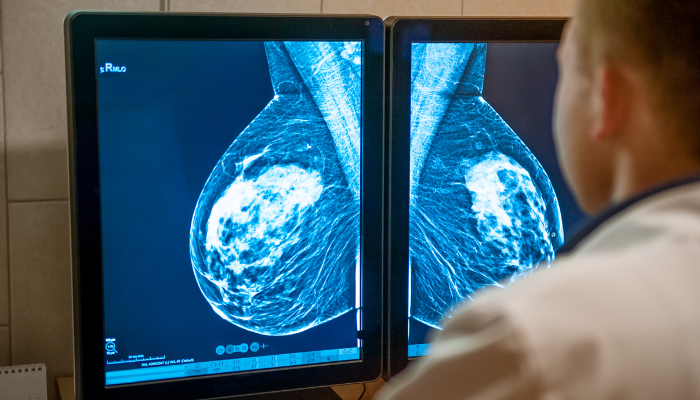

Un equipo del Instituto Karolinska, de Estocolmo, desarrolló un método para el diagnóstico de cáncer de mama que se caracteriza por un diferencial: busca determinar cuál es el mejor tratamiento para cada paciente.